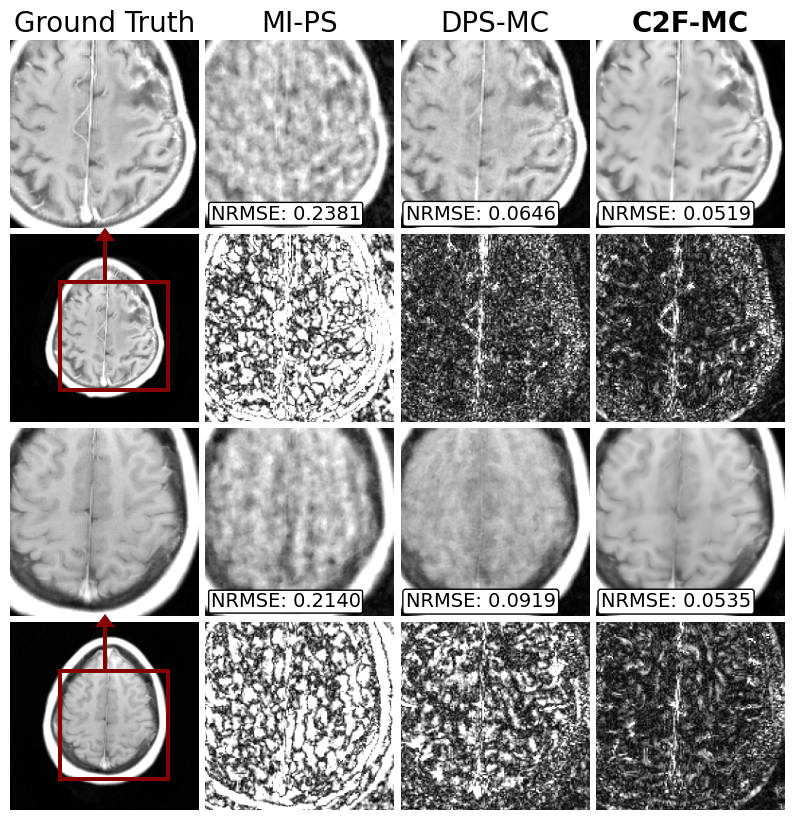

Fig. 3: Non-rigid motion correction and reconstruction on multicoil data with 8 simulated motion states each undersampled by 64x. Error x10 is shown below each image. Our method (C2F-MC) outperforms the same method using standard diffusion (DPS-MC) and the state-of-the-art rigid motion correction (MI-PS).

We test our method under the disjoint 2D sampling regime, designing 𝐌𝐌\mathbf{M}bold_M to collect just 1/8 of k𝑘kitalic_k-space. However, we introduce 8 different motion states; thus, each 𝐌(τ)superscript𝐌𝜏\mathbf{M}^{(\tau)}bold_M start_POSTSUPERSCRIPT ( italic_τ ) end_POSTSUPERSCRIPT has an acceleration of 64x, with a maximum displacement of at most 15 pixels. Results are shown in Fig. 3. We compare our results (C2F-MC) to the same method on a standard diffusion model (DPS-MC) and the state-of-the-art rigid motion correction (MI-PS). Both C2F-MC and DPS-MC used 10 alternating minimization iterations during inference, uniformly across the sampling process.

Our method outperforms all methods, demonstrating the effectiveness of coarse-to-fine denoising compared to standard diffusion methods. There is less hallucination and missing reconstruction details compared to the other methods. Furthermore, we perform better than MI-PS, as its rigid motion assumption does not generalize to non-rigid motion.

Test Statistics: Over 100 simulated non-rigid motion-corrupted images, the NRMSE (Normalized Root Mean Squared Error) statistic of C2F-MC was 0.058 ±plus-or-minus\pm± 0.0032.